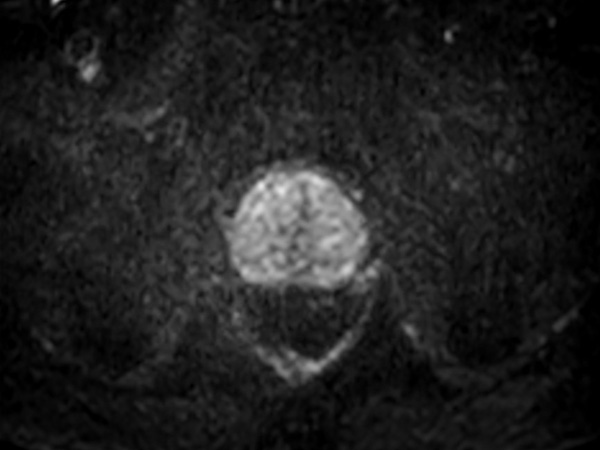

Fast Prostate imaging with SmartSpeed Precise

Kumamoto Chuo Hospital Japan

Used Solution